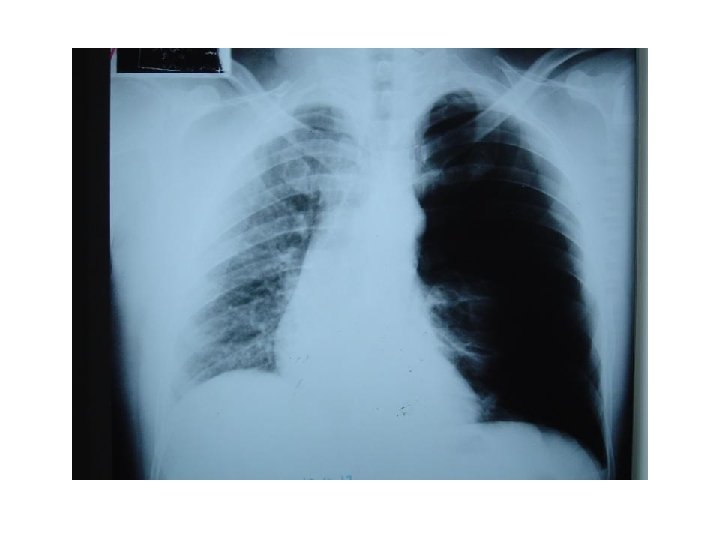

Left bronchus syndrome , Next slide Plzzz =) Notice , the Trachea is pulled to left side. . WHY ? cuz of fibrosis there is loss of space , loss of ventilation in the left side , the left lung is smaller in size , infective , bronchioectatic , it will pull the trachea toward it.

Left bronchus syndrome : Chronic condition , it is the end sequelae ﺍﻟﻨﺘﻴﺠﺔ ﺍﻟﻨﻬﺎﺋﻴﺔ of lung destruction due to TB In the previous slide , notice the bronchioectatic changes all over the lung ! Rt lung : pt still can breath from it , although it has apical scarring , Rt upper zone infiltration. Lt Lung : has Abcess cavity , Air Fluid levels , cystic bronchiectasis. If we did bronchoscopy , bronchoalveolar lavage , we will see the Fast Bacilli of Mycobacterium TB , which are resistant to 1 st , 2 nd and 3 rd line anti-TB medications ! ﻧﺘﻴﺠﺔ ﺑﺆﺮﺓ ﺍﻟﺘﻬﺎﺑﻴﺔ Left bronchus syndrome : The study was done at KKUH , if u r interested : http: //www. ncbi. nlm. nih. gov/pmc/articles/PMC 462386/pdf/thorax 00339 -0050. pdf 0